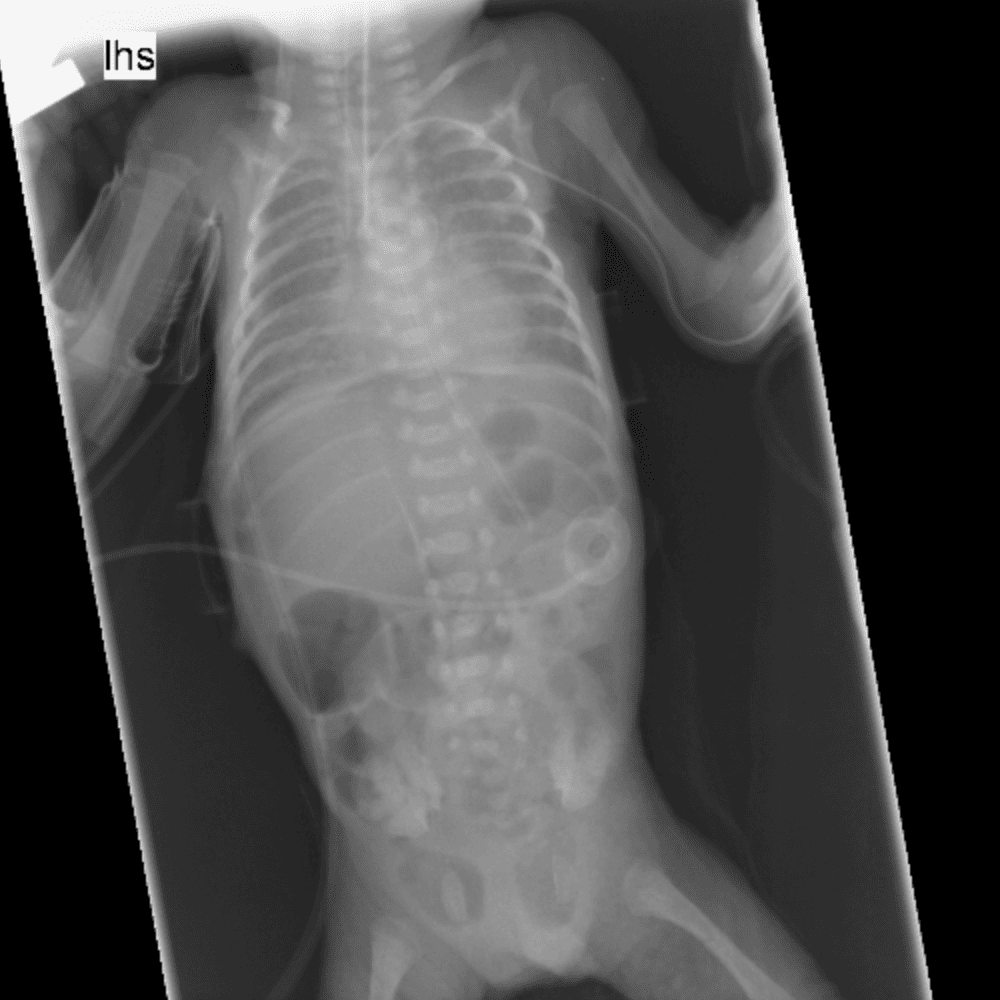

Peds Abdomen

Practice

Simulates call by including subtle or difficult cases and some normals.

30 cases